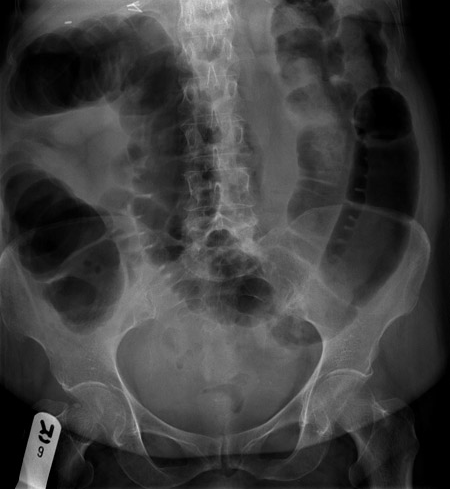

Q

What does this show?

Caecal volvulus

• massively dilated caecem no long lies in RIF

• small bowel now occupies this space